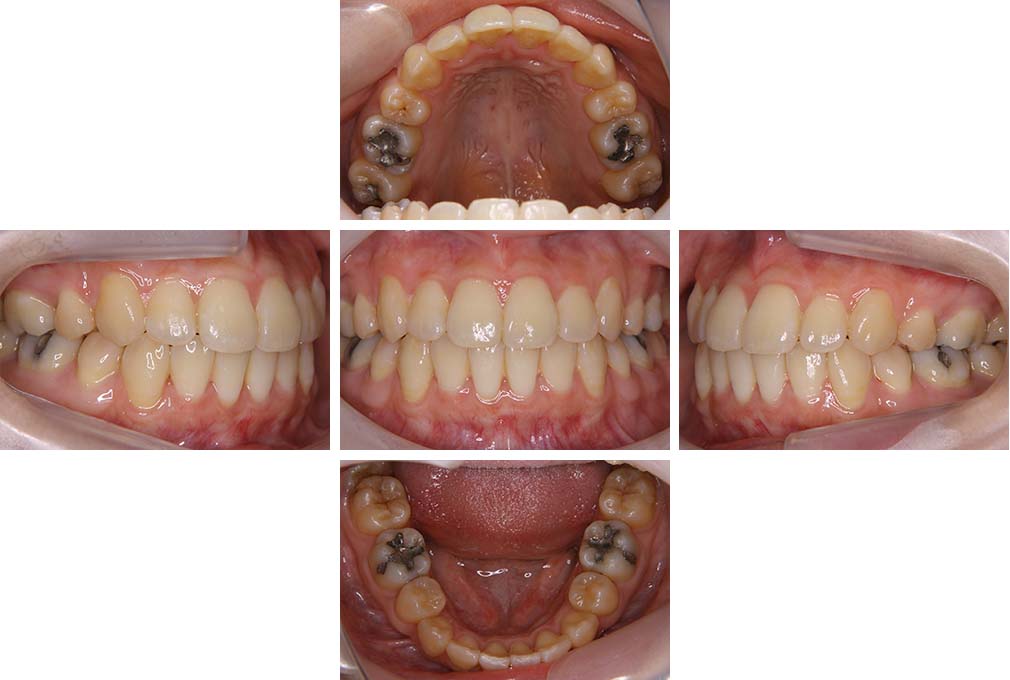

CASE:04

アングルⅢ級傾向を持つ叢生

初診時年齢 22歳

性別 女性

治療費の目安 105万円程度(治療開始時)

上顎右側犬歯が唇側に転位していることを主訴に県内歯科医院から紹介来院された。骨格的にはⅢ級傾向で上顎右側犬歯が唇側転位となり、側切歯が口蓋側に転位していた。下顎前歯が叢生になっていることも相まって上下の正中線は右側に大きくずれていた。アングルⅢ級傾向を持つ上下顎前歯部叢生と診断した。

上下顎小臼歯を抜歯していただき上顎舌側、下顎唇側マルチブラケット装置を使用して動的治療を行った。矯正用ゴムの使用など協力状態も良く、正中線の大きな移動があったのも関わらず2年10カ月で装置を撤去し保定へ移行した。保定移行後14年が経過し、ご息女の診察でご来院いただいていたことから、口腔内を拝見したが、下顎前歯のわずかなずれがあったものの大きな歯列の乱れはなく歯列は安定していた。動的治療期間2年10カ月間。

治療前

22歳6か月

治療後

動的治療期間2年10カ月間

25歳6か月

治療終了

動的治療終了後2年2カ月

28歳8か月

14年経過

動的治療終了後14年7カ月

40歳1か月